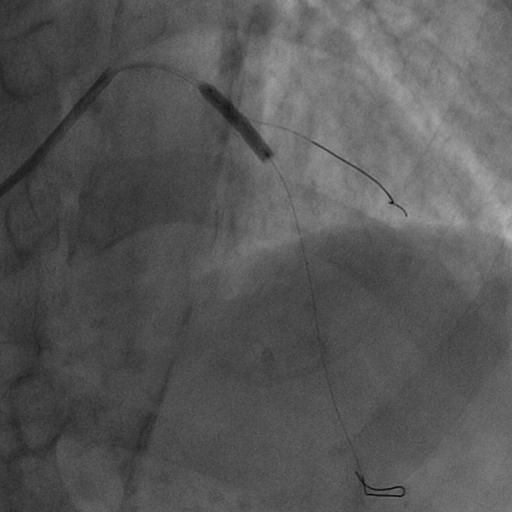

カテーテル治療(PCI)

直径2mmの管(カテーテル)を血管の中に挿入し、冠動脈の治療を行います。当院では、負担の少ない手首からのカテーテル治療を基本としています。局所麻酔で1時間程度の治療時間です。冠動脈の細くなった部分を、バルーン治療、またステントと呼ばれる金属の筒を入れて広げます。重症症例に対する補助循環装置(IABP、PCPS)も常備しております。

左前下行枝の高度狭窄

薬剤溶出性ステント留置

治療後